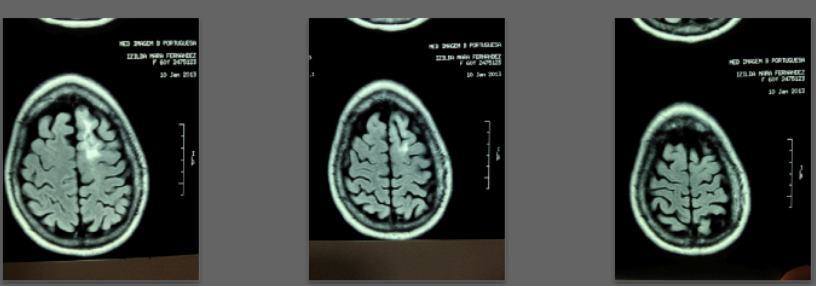

Before/after MRI images for one of 1,000+ patients of Dr. Coimbra

2008 Convulsive seizures Diagnosis: Balo’s concentric hemiparesis

Starting daily dose 25,000 IU; increased in stages to 80,000 IU on October 28, 2010. Asymptomatic since 2010.

2008 MRI

2013 MRI